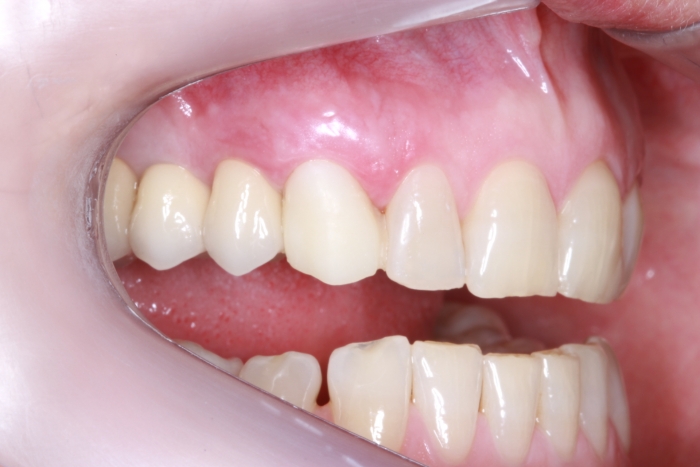

Foto lateral com protese definitiva 22-08-17 - Clínica Cliniface

Foto lateral com protese definitiva 22-08-17